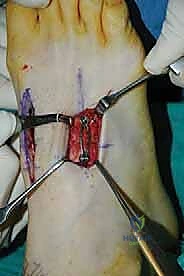

1. Incisions and Initial Exposure

We're going to use two well-spaced longitudinal incisions to maximize our skin bridge and minimize the risk of wound complications.

Medial Incision (First and Medial Second TMT Joints):

- "Fellows, let's make our first incision. It's a 4-cm longitudinal incision, centered over the lateral third of the first TMT joint. This incision runs roughly between the extensor hallucis longus (EHL) and the extensor hallucis brevis (EHB) tendons. Visualize that interval."

- "Carefully deepen your dissection through the subcutaneous tissue. Remember, the dorsal cutaneous nerves are extremely superficial here. Use a sharp scalpel initially, then switch to blunt dissection with Metzenbaum scissors or a small hemostat. We want to avoid any aggressive retraction on the skin edges."

- "Now, identify the EHL tendon medially and the EHB tendon laterally. We're working in this interval. As we deepen, be vigilant for the deep peroneal nerve and the dorsalis pedis artery. They lie just deep to the medial aspect of the EHB tendon, coursing towards the first web space. Gently retract these structures medially with a small Hohmann or a blunt army-navy retractor. Never use sharp retractors here."

- "Once we've identified and protected these vital structures, we can identify the capsule of the first TMT joint. You can often feel the joint line by gently mobilizing the first metatarsal. Incise the capsule transversely, in line with the joint. This minimizes periosteal stripping, which can compromise blood supply to the fusion site."

- "Now, carefully dissect proximally between the first and second metatarsal bases to expose the medial aspect of the second TMT joint. Remember, the second TMT joint is recessed more proximally relative to the first."

Lateral Incision (Lateral Second and Third TMT Joints):

- "Next, let's make our second incision. This is another 4-cm longitudinal incision, centered directly over the third TMT joint."

- "Again, deepen carefully through the subcutaneous tissue, being mindful of the dorsal cutaneous nerves. These are even more prevalent laterally. Blunt dissection is your friend here."

- "You'll encounter the extensor digitorum brevis (EDB) muscle belly. Typically, we cannot simply retract the EDB plantar without causing undue tension on the neurovascular structures or the muscle itself. Therefore, we will split the EDB longitudinally, directly in line with our skin incision. This provides excellent exposure without excessive soft tissue trauma."

- "Once the EDB is split, identify the capsule of the third TMT joint. Again, split the periosteum and capsule in line with the joint to avoid excessive stripping."

- "Through this incision, we can also expose the lateral aspect of the second TMT joint and the space between the second and third metatarsal bases."